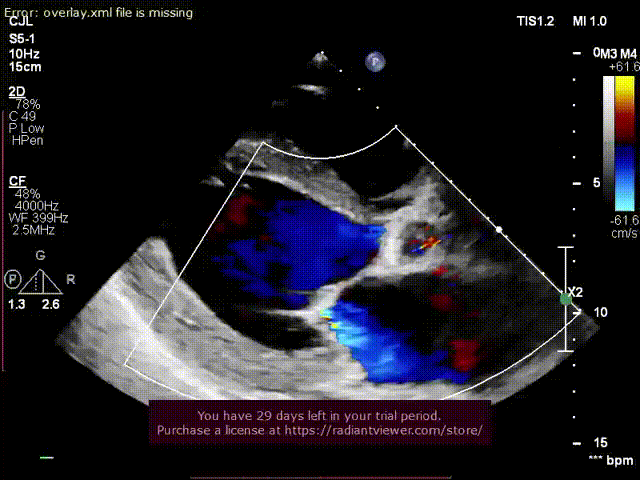

超声术后评估:

超声显示假体瓣膜形态良好,工作正常,少量瓣周漏。

超声显示假体瓣膜形态良好,工作正常,微量瓣周漏。